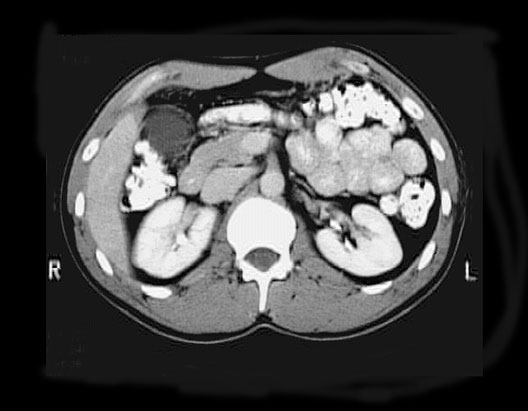

Abdominal CT

1. Hepatic flexure

2. Gall Bladder

3. Inferior Vena Cava

4. Abdominal Aorta

5. Jejunum

6. Descending Colon

7. Left Kidney

8. Spinal Canal

9. Right Kidney